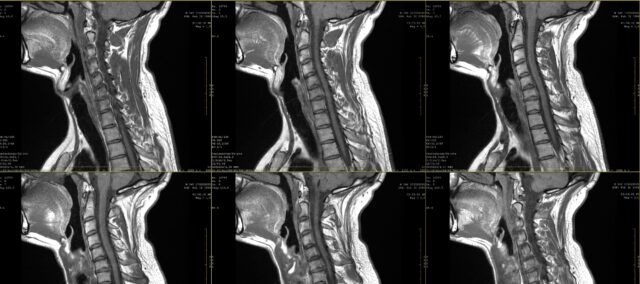

Tässä tutkimuksessa tutkittiin radikulaarisen kivun piirrosten ja magneettikuvauslöydösten välistä vastaavuutta, ja siihen osallistui osallistujia, joilla oli ollut kahden kuukauden ajan jatkuvaa kipua ja joilla oli magneettikuvauksessa diagnosoitu kaularangan radikulopatia. Diagnoosin teki neurokirurgi kliinisten tietojen ja radiologin arvioimien magneettikuvauslöydösten perusteella.

Kipupiirrokset tehtiin vartalokaavioihin sekä etu- että takanäkymästä. Nämä kaaviot näytettiin sitten neljälle lääkärille (2 kirurgille ja 2 fysioterapeutille), jotka eivät tienneet, mikä hermojuuri oli mukana magneettikuvauksessa. He saivat vain tiedon, että kaikilla potilailla, joiden kipupiirustukset heille esitettiin, oli diagnosoitu kaularangan radikulopatia vain yhdellä tasolla C4:n ja C7:n välillä. Potilaan kipupiirroksen perusteella heidän oli tunnistettava, mikä selkärangan taso oli kyseessä. Magneettikuvauksella todennetun selkärangan tason ja kliinikon kipupiirroksen perusteella tekemän arvioinnin välinen yksimielisyys arvioitiin kappa-arvion avulla. Lisäksi arvioijien välistä yhteisymmärrystä tutkittiin myös kappa-tilastolla. Kappa-arvot tulkittiin seuraavasti: